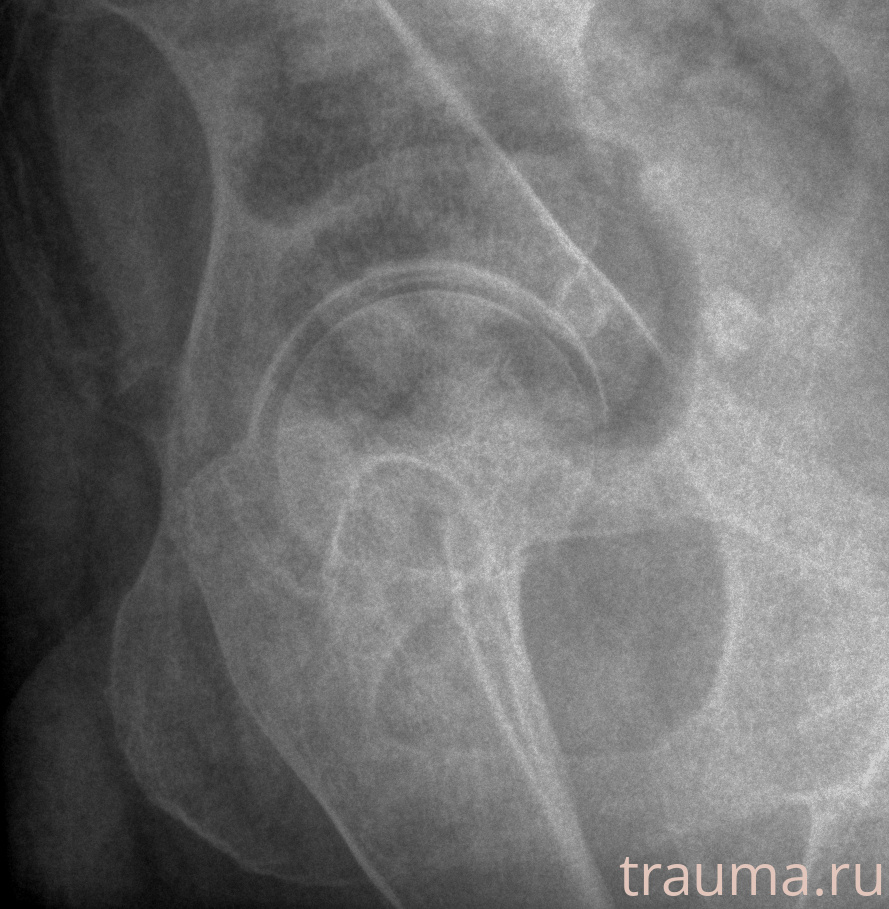

Рентгенограммы

Рентген на дому: по вашему адресу приезжает врач-рентгенолог, травматолог-ортопед с мобильным рентгеновским аппаратом, проводит диагностику травмы или заболевания, делает необходимые рентгенограммы, дает рекомендации по дальнейшему лечению. Получить качественные снимки в домашних условиях возможно благодаря уникальной методике, разработанной МосРентген Центром для института  Склифосовского